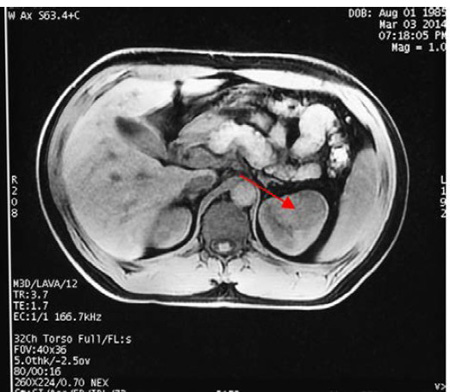

10、双肾磁共振平扫

+增强

、醛固酮;影像学提示左肾占位性病变;肾血管未见异常;

提示高肾素、高醛固酮,查双肾超声及双肾MRI提示右肾上极存在占位,临床诊断主要考虑肾素瘤。临床上需要鉴别肾性或肾血管性高血压,肾血管性高血压一般表现为中重型血压升高,一般对降压药物效果不佳,有时呈急进性或恶性高血压,上腹部脐周和腰背部有时常可闻及收缩期或连续性血管杂音

4、B 超和CT是最常用的影像检查手段。B超检查病变可表现为肾皮质内低或中强各种回声。本次报告的第二例患者可能由于存在瘤体内的出血而显示不均质回声。CT平扫+动态增强扫描是有效的定位诊断方法,敏感性接近100%。CT平扫常表现稍低至等密度,增强后在动脉期常与肾实质其他部位一致,但在门脉期或延迟期可有轻-中度强化而与周期肾实质存在差异。